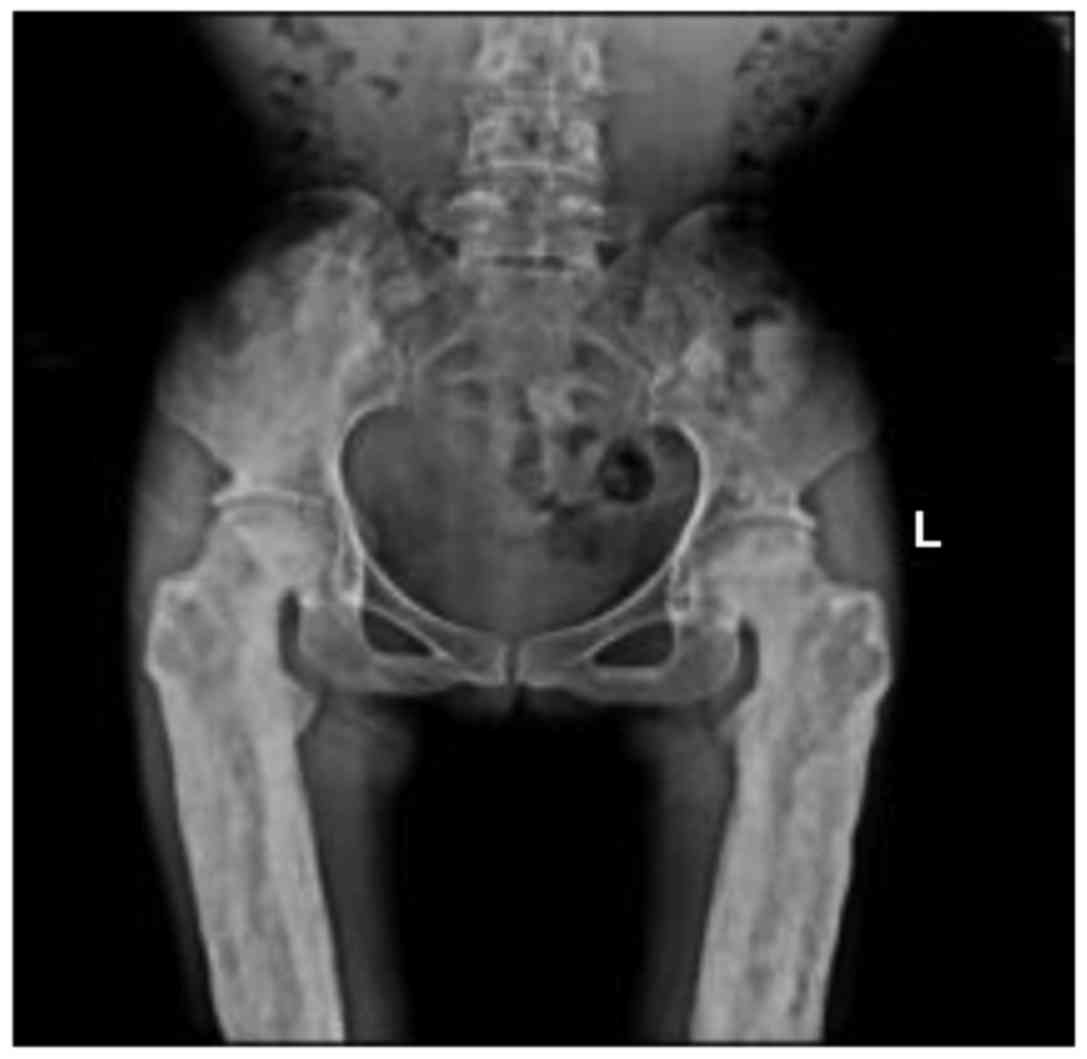

X-ray Images Showing Features Of Camurati-Engelmann Disease In The

X-ray images showing features of Camurati-Engelmann disease in the www.researchgate.net

engelmann camurati thickening